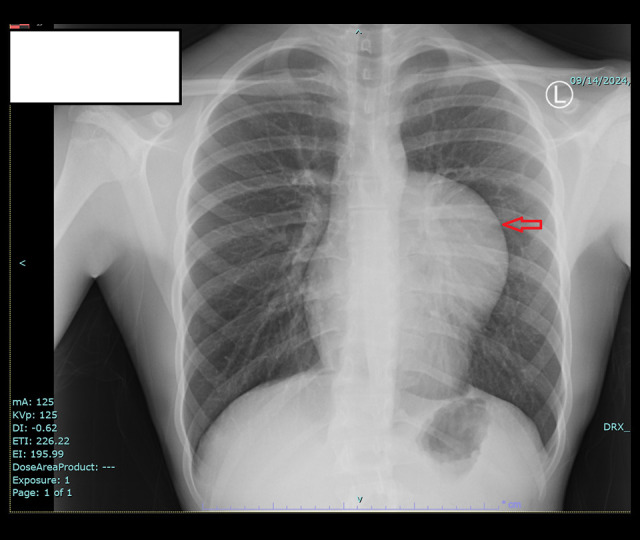

背景:包虫病仍然是一个主要的临床问题,特别是在流行包虫病的地区。这种寄生虫感染是由棘球绦虫引起的。肝和肺是受影响最严重的器官。尽管肺是最常见的胸内脏器,但肺外的胸内包虫病并不常见。然而,原发性纵隔包虫病是一种罕见的疾病,而胸腺的原发性包虫病更是极为罕见。尽管视频胸腔镜手术在胸外科领域发挥着重要作用,但其在治疗胸部包虫病中的作用尚不明确。本文报告一例17岁男性胸腔镜下胸腺包虫病原发治疗。病例报告一名17岁男性因胸闷、呼吸短促3个月前来就诊。胸片上可见明显的混浊。随后的计算机断层扫描(CT)显示在左半胸有一个大的、界限明确的囊性病变,尺寸为6.5×7×11 cm。他后来被安排进行VATS手术切除囊肿,发现囊肿与胸腺有连续性。整体胸腺切除术,以确保完全切除膀胱周围。结论:该病例的独特之处不仅在于它描述了一种罕见的包虫病部位,还在于所采用的切除技术。根据我们的文献回顾,这是最早报道的通过胸腔镜切除该部位包虫病的病例之一。此外,与开胸手术相比,VATS恢复更快,术后疼痛减轻,在类似病例中的应用有待进一步探讨。

BACKGROUND Hydatid disease remains a major clinical concern, particularly in regions where it is endemic. This parasitic infection is caused by Echinococcus species. The liver and lungs are the most affected organs. Although the lungs are the most commonly affected intrathoracic organ, extrapulmonary intrathoracic hydatid disease is uncommon. However, primary mediastinal hydatid disease is a rare entity, and a primary hydatid cyst in the thymus is extremely rare. Although video-assisted thoracoscopic surgery (VATS) plays an important role in the field of thoracic surgery, its role in treating hydatid disease in the chest is not well established. This report describes a case of 17-year-old male presenting with primary hydatid cyst of the thymus treated thoracoscopically. CASE REPORT A 17-year-old male presented to our clinic with chest tightness and shortness of breath of 3 months duration. A well-defined opacity was identified on chest radiography. Subsequent computed tomography (CT) revealed a large, well-defined cystic lesion in the left hemithorax, measuring 6.5×7×11 cm. He was later scheduled for VATS to resect the cyst, which was found to be in continuity with the thymic gland. An en bloc thymectomy was performed to ensure complete peri-cystectomy. CONCLUSIONS This case is unique not only because it describes a rare location of hydatid disease, but also due to the technique of resection that was used. Based on our literature review, this is among the earliest reported cases of a hydatid cyst in this location resected via thoracoscopy. Furthermore, compared with thoracotomy, VATS offers faster recovery and reduced postoperative pain, and its application in similar cases should be further explored.